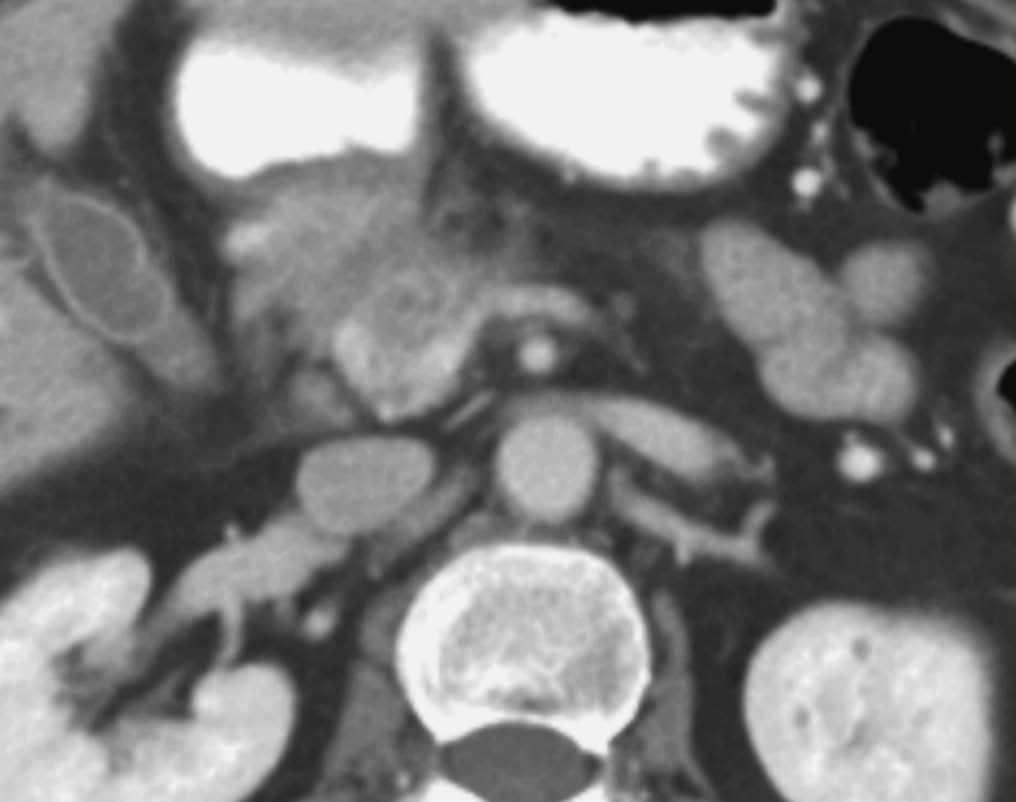

La TC helicoidal permitió, además, llevar a cabo un estudio detallado de los pequeños vasos arteriales y venosos peripancreáticos24-26 (fig. 2), mostrando mejores resultados que la angiografía por sustracción digital en el diagnóstico de la invasión vascular por cáncer de páncreas27. La valoración de estas pequeñas estructuras vasculares mejora el rendimiento de la TC en la estadificación tumoral28,29. La posibilidad de reconstruir en diferentes planos del espacio las imágenes axiales obtenidas ha sido evaluada por algunos autores30,31, obteniendo un mayor rendimiento de la TC para determinar la invasión vascular, fundamentalmente venosa, cuando las secciones transversas se interpretan en combinación con las reconstrucciones multiplanares que cuando se interpretan únicamente las secciones transversas (92-96% frente a 69-70%) (fig. 3).

Fig. 2.--Estudio de tomografía computarizada con contraste endovenoso en fase pancreatográfica en un paciente con neoplasia del cuerpo pancreático. Múltiples vasos mesentéricos dilatados secundarios a la infiltración venosa portomesentérica tumoral (flechas).